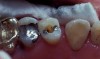

Fig 3. After decay and old restorative material removal to access the canal orifices, the tooth is potentially left in a weakened condition (left); after a pre-endodontic buildup to reinforce the remaining tooth while allowing access to the canals for endodontic treatment (right).

Figure 3